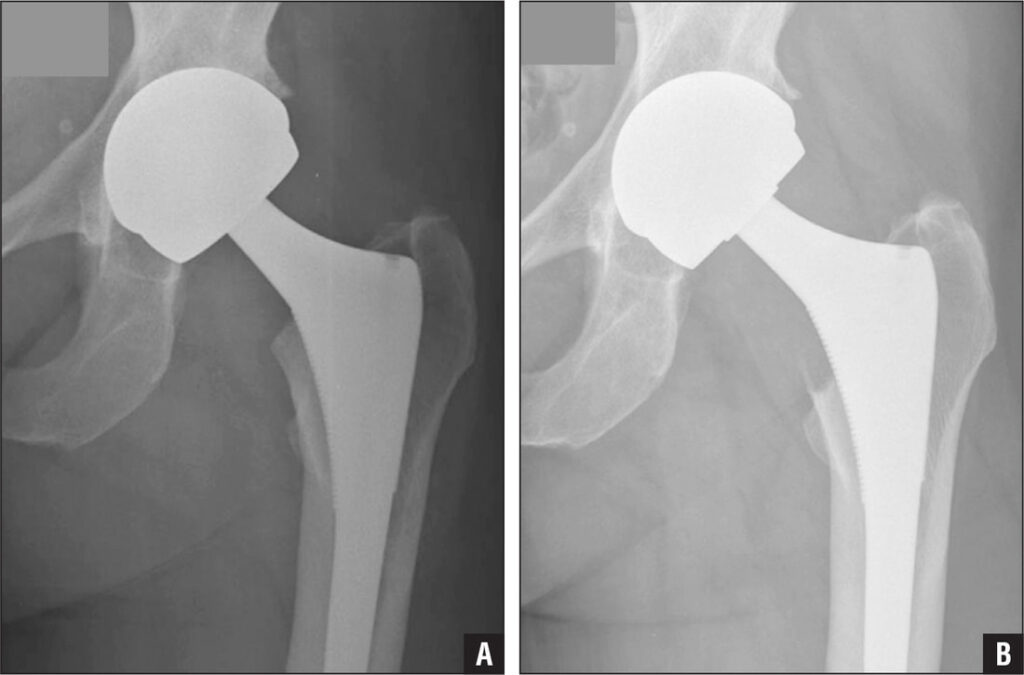

Hip replacement surgery is a procedure in which a surgeon removes damaged sections of the hip joint and replaces them with artificial parts. The hip is a ball-and-socket joint. The ball, at the top of the femur, fits into a rounded socket in the pelvis.

During the surgery, the damaged femoral head is removed and replaced with a metal stem that is placed into the femur. A metal or ceramic ball is then placed on the upper part of the stem. This ball replaces the damaged femoral head that was removed. The damaged cartilage surface of the socket is removed and replaced with an artificial socket. These components are designed to replicate the natural movement of the hip joint.